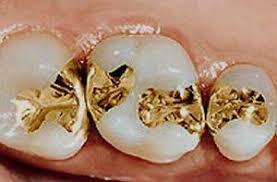

• Lamina de oro.

Lamina de oro.

La lámina de oro fue introducida por primera vez en Estados Unidos por Robert Woofendale en 1795 y fue uno de los primeros materiales disponibles para la restauración de dientes.